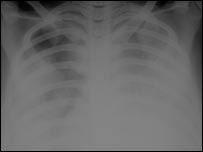

Radiografia ajuda a prever mortalidade por gripe aviária

Radiografia de pulmão

As chapas de raio-x dos pacientes mostravam diferentes padrões de evolução da doença

Médicos da Universidade de Oxford anunciaram ter descoberto como prever o quão mortal é um caso humano de gripe aviária verificando uma radiografia do pulmão da pessoa infectada.

As chapas de raio-x dos pacientes mostravam diferentes padrões de evolução da doença. Segundo os radiologistas de Oxford, estes padrões podem indicar que tipo de tratamento cada paciente necessita.

“A anormalidade mais comum que encontramos era consolidação multifocal, que normalmente representa pus e infecções em pacientes com febre e tosse”, disse Nagmi Qureshi, especialista em radiologia da Universidade de Oxford, que analisou 98 radiografias de pulmão dos 14 pacientes.